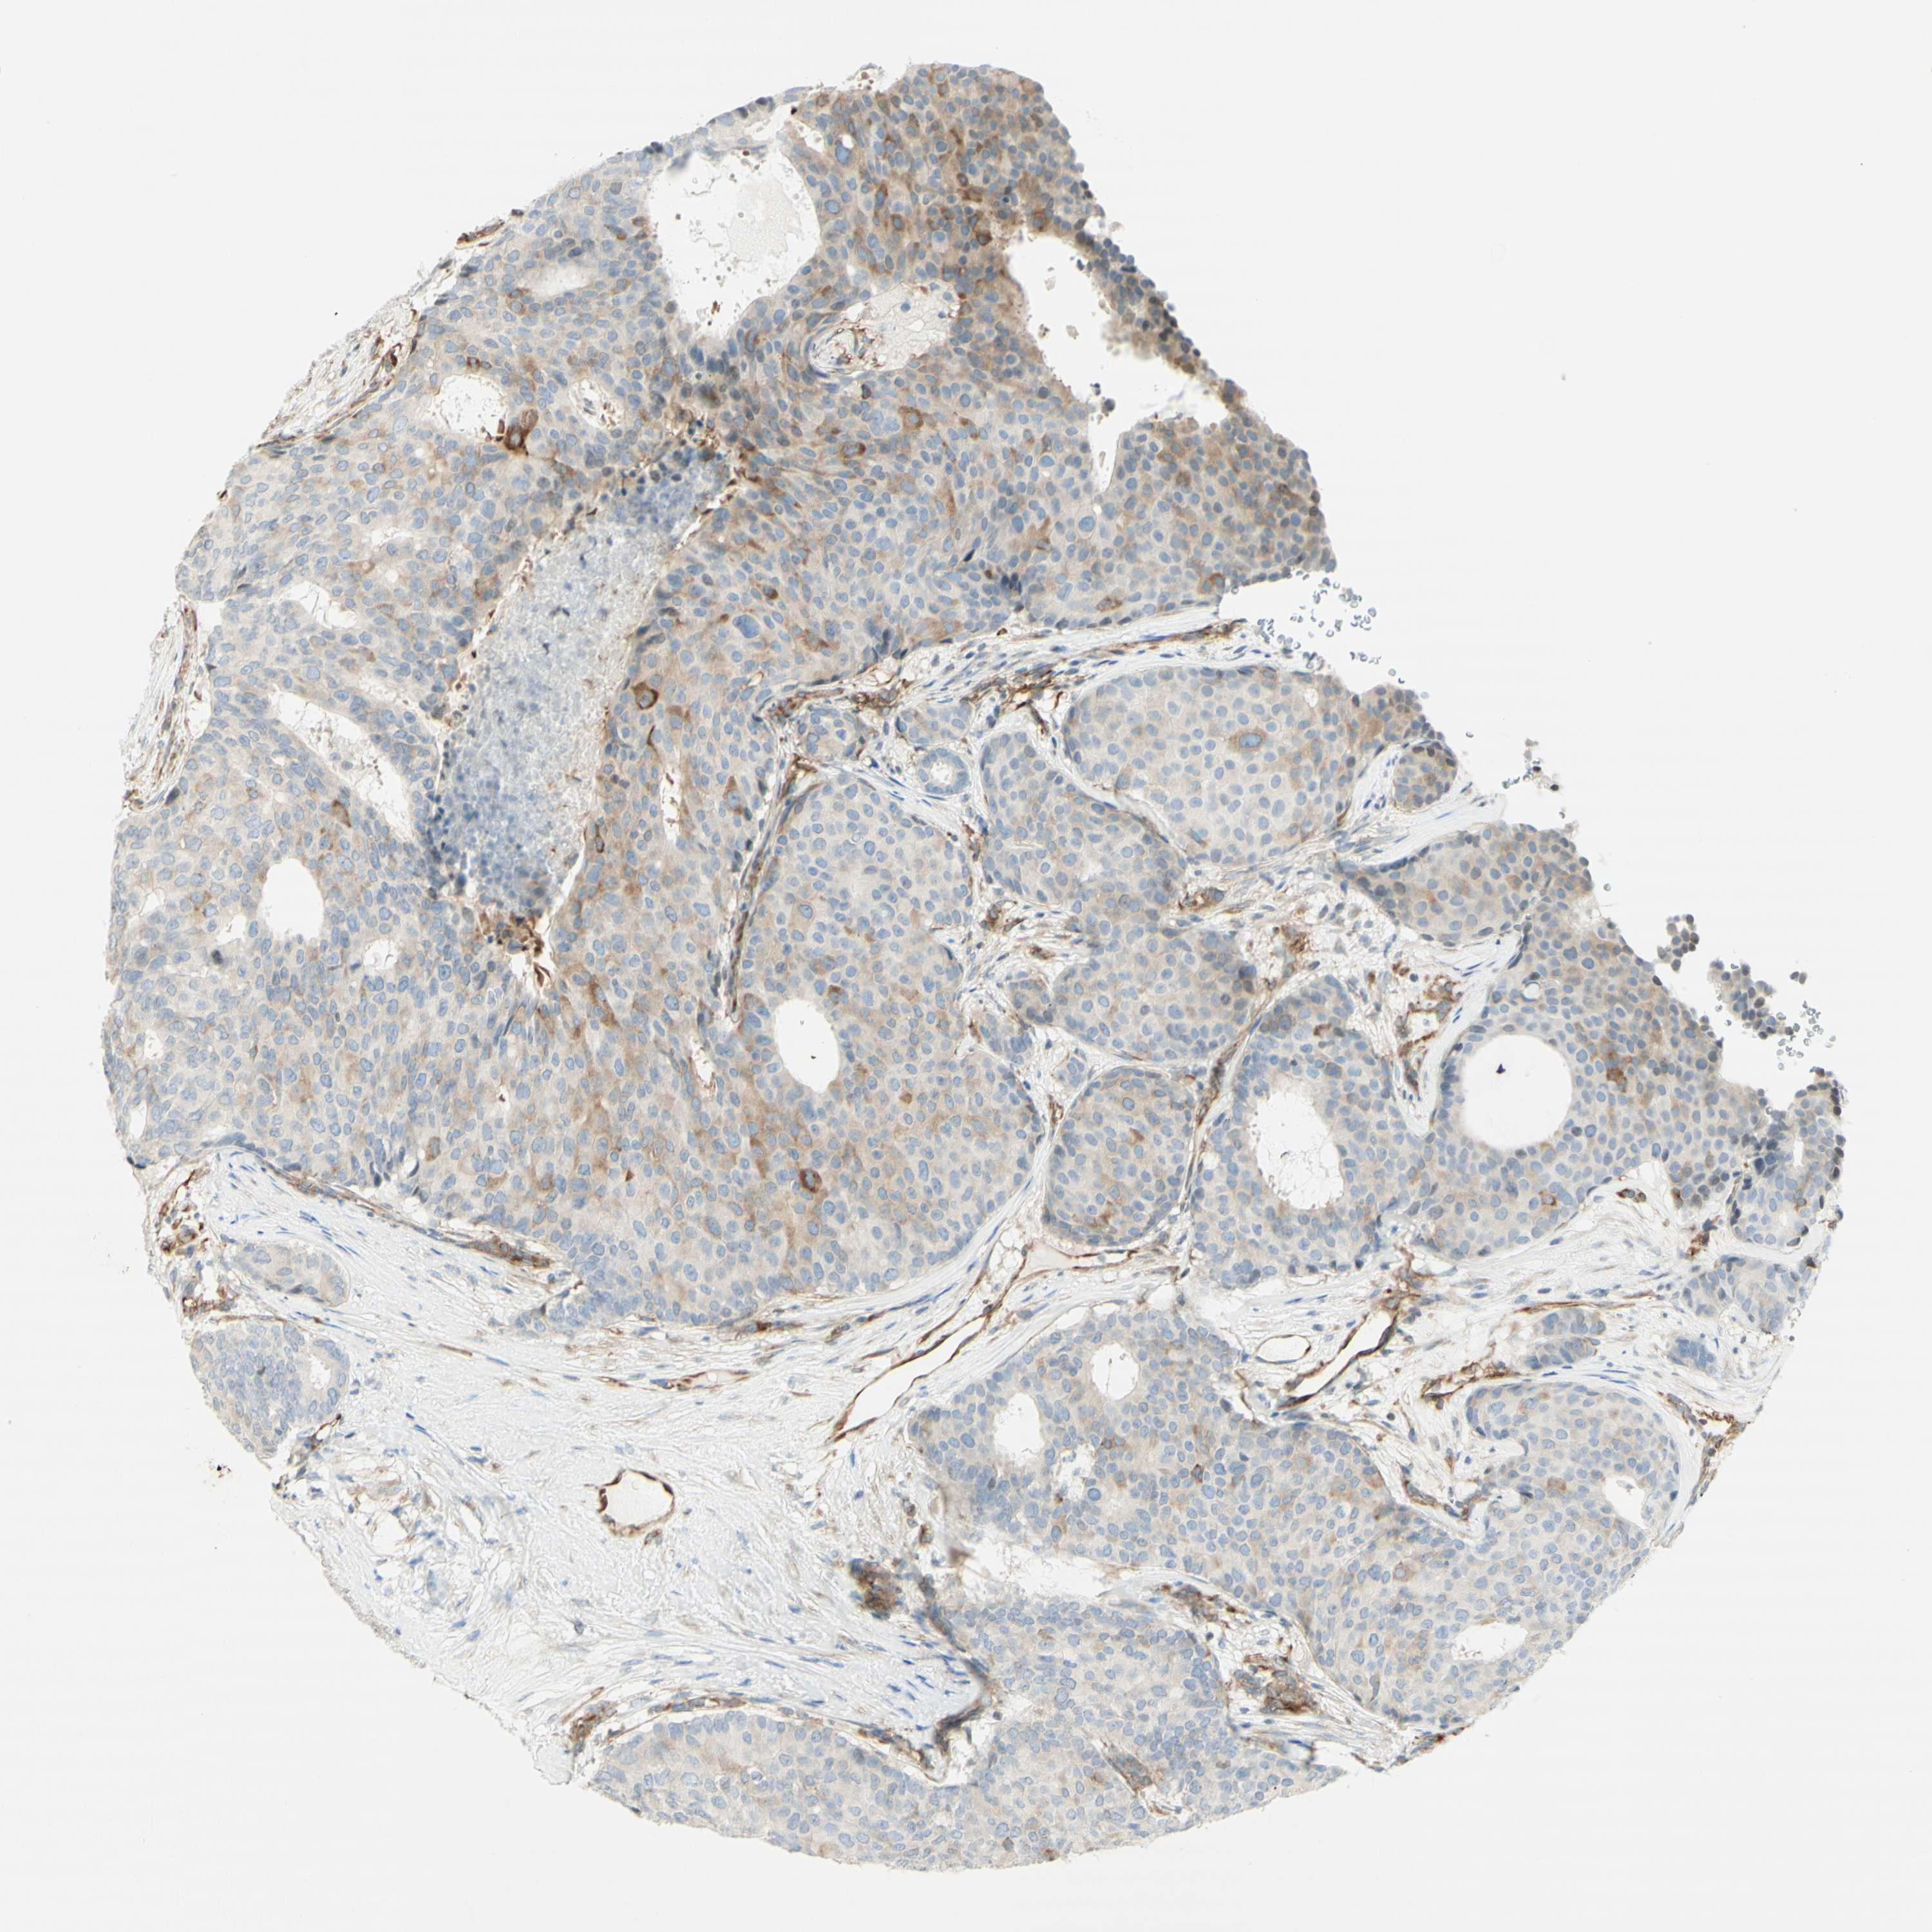

CANCER BREAST CANCER Show tissue menu

BRCA TCGA BRCA VALIDATION PROTEIN EXPRESSION

ANTIBODIES

AND

VALIDATION